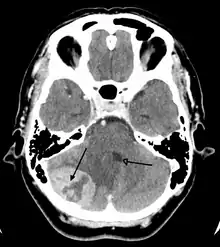

![]() انبثاث الورم الدماغي في نصف الكرة الدماغية الأيمن بسبب سرطان الرئة يظهر بالتصوير بالرنين المغناطيسي الموزون بT1 مع التباين داخل الوريد. انبثاث الورم الدماغي في نصف الكرة الدماغية الأيمن بسبب سرطان الرئة يظهر بالتصوير بالرنين المغناطيسي الموزون بT1 مع التباين داخل الوريد. | |

الأورام الثانوية من الدماغ هي من النوع الذي ينتشر، وتكون قد غزت الدماغ من السرطانات التي تنشأ في الأجهزة الأخرى. هذا يعني أن الورم نشأ في عضو اخر من الجسم ثم انتشر عن طريق نظام الأوعية الدموية والنظام اللمفاوي. وبعد ذلك وصلت لمجرى الدم، واخيرا استقرت في الدماغ لتستمر في النمو والانقسام. أصبحت الأورام الثانوية شائعة في المرضى الذين يعانون من سرطان في اي مكان من الجسد غير قابل الشفاء. الأنواع الأكثر شيوعا من السرطانات التي أدت إلى إحداث أورام ثانوية في الدماغ هي: سرطان الرئة، سرطان الثدي، سرطان الجلد الخبيث، سرطان الكلى وسرطان القولون (بالترتيب التنازلي تبعا للتكرار).